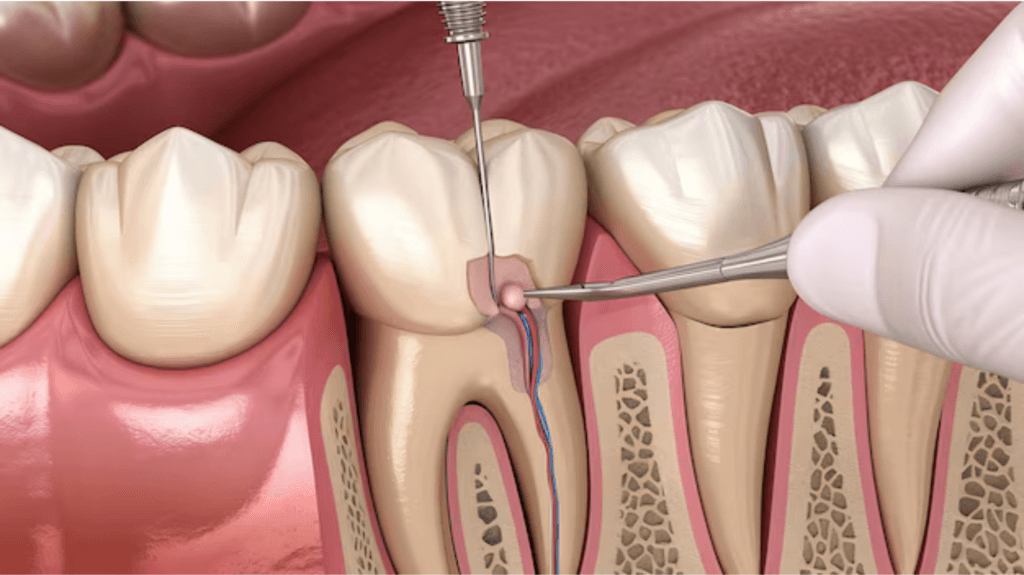

- Dentistry

Treatments